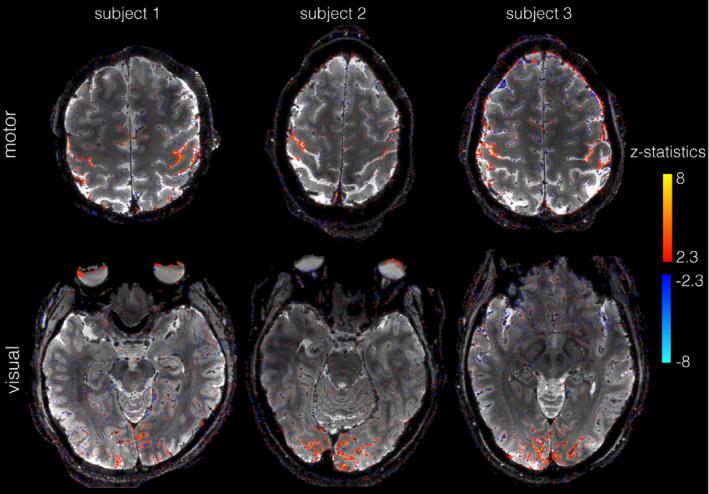

An improved, completely self-navigated version of the TURBINE sampling scheme was designed for fMRI at 7 Telsa. To demonstrate the image quality and spatial specificity of the acquisition, thin-slab visual and motor BOLD fMRI at 0.67 mm isotropic resolution (16 mm slab, TRvol = 2.32 s), and 0.8 × 0.8 × 2.0 mm (whole-brain, TRvol = 2.4 s) data were acquired. To prioritize the high spatial fidelity, we employed a temporally regularized reconstruction to improve sensitivity without any spatial bias.

RESULTS

TURBINE images provide high structural fidelity with almost no distortion, dropout, or T * blurring for the thin-slab acquisitions compared to conventional 3D EPI owing to the radial sampling in-plane and the short echo train used. This results in activation that can be localized to pre- and postcentral gyri in a motor task, for example, with excellent correspondence to brain structure measured by a T -MPRAGE. The benefits of TURBINE (low distortion, dropout, blurring) are reduced for the whole-brain acquisition due to the longer EPI train. We demonstrate robust BOLD activation at 0.67 mm isotropic resolution (thin-slab) and also anisotropic 0.8 × 0.8 × 2.0 mm (whole-brain) acquisitions.

方法

为在 7T 下进行 fMRI,设计了一种改进的、完全自我导航的 TURBINE 采样方案。为了展示采集的图像质量和空间特异性,我们在 0.67 毫米各向同性分辨率(16 毫米片层,TRvol = 2.32 秒)下进行了薄切片视觉和运动 BOLD fMRI,以及 0.8×0.8×2.0 毫米(全脑,TRvol = 2.4 秒)数据采集。为了优先考虑高空间保真度,我们采用了时间正则化重建来提高灵敏度,而没有任何空间偏差。

结果

与传统的 3D EPI 相比,TURBINE 图像提供了几乎没有失真、缺失或 T * 模糊的高结构保真度,这是由于在平面内进行的径向采样和使用的短回波链。这导致例如在运动任务中,可以将激活定位到中央前回和中央后回,与 T -MPRAGE 测量的大脑结构具有极好的对应关系。由于 EPI 链较长,TURBINE(低失真、缺失、模糊)的优势对于全脑采集会降低。我们在 0.67 毫米各向同性分辨率(薄片)下证明了稳健的 BOLD 激活,并且还在各向异性 0.8×0.8×2.0 毫米(全脑)采集下证明了稳健的 BOLD 激活。